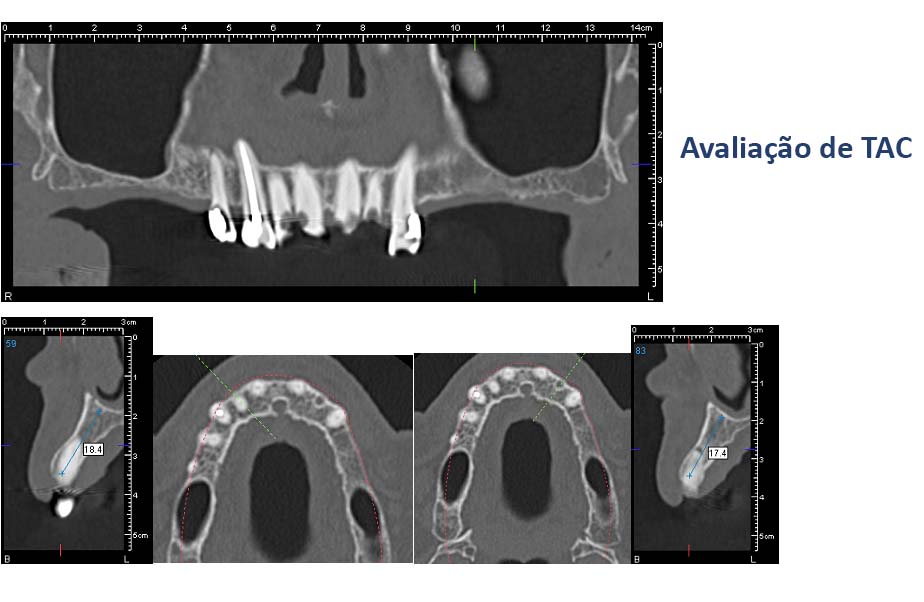

• If necessary additional exames are taken (TAC)